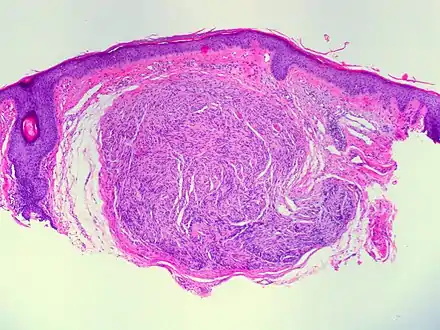

Skin tumors(palisaded encapsulated neuroma)